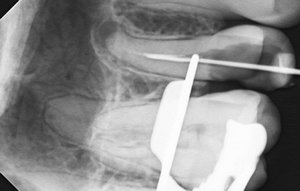

Отвалилась старая пломба, которую ставили девять лет назад. Пришел к стоматологу, она осмотрев сказала, что надо зачистить и заново запломбировать. Начав процедуру чистки, она попробовала пошатать зуб, потом сказала, что нужно сделать снимок. Снимок сделали, ее вердикт — надо удалять зуб, поскольку пошло воспаление вокруг корней, если его лечить со штифтами или еще как, через некоторое время он снова даст о себе знать и все равно придется удалить.

Смысл конечно всегда есть, но если диагноз доктора подтвердится (воспаление на корнях), то скорее всего зуб придётся удалить.